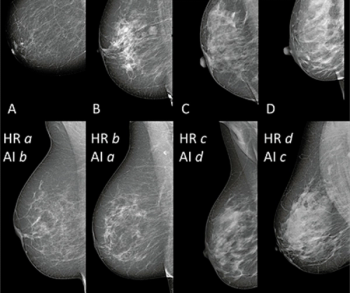

The artificial intelligence (AI) model reportedly had an 89.3 accuracy rate in differentiating between non-dense and dense breasts on mammography scans, and a 90.4 percent rate of agreement with human radiologist reviewers.